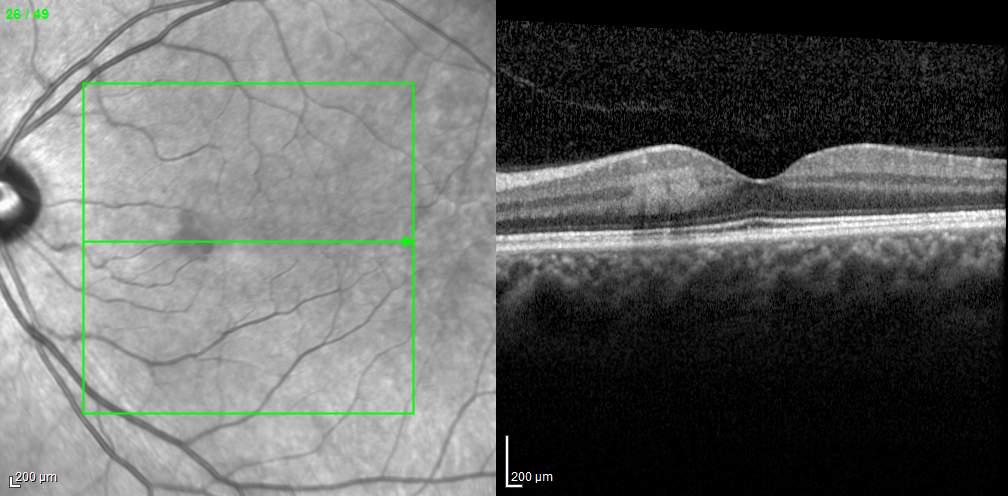

MNV may also develop in patients with central serous chorioretinopathy. In this condition, the pathogenesis of MNV is not yet fully understood. It is known that it can occur after laser photocoagulation or photodynamic therapy as a compensatory response to treatment; however, MNV may also develop in cases without history of laser treatment. In these cases, MNV may develop in a manner similar to AMD, where the rupture of Bruch’s membrane due to chronic RPE changes and long-standing serous pigment epithelium detachment allows for the growth of Type 1 neovascularization.33–36 (Figure 6)

Figure 6. Multimodal imaging of Type 1 macular neovascularization secondary to central serous chorioretinopathy. Fluorescein angiography (A and B) showing pinpoints of hyperfluorescence with leakage in the late phase. Indocyanine green angiography (C and D) displaying the central hyperfluorescent area and the adiacent area of choridal hyperpermeability. Fundus autofluorescence (E) revealing abnormalities of retinal pigment epithelium. The en face of optical coherence tomography angiography (F) showing the neovascular network and the B-scan displaying the shallow irregular retinal pigment epithelium elevation with subretinal fluid (G).